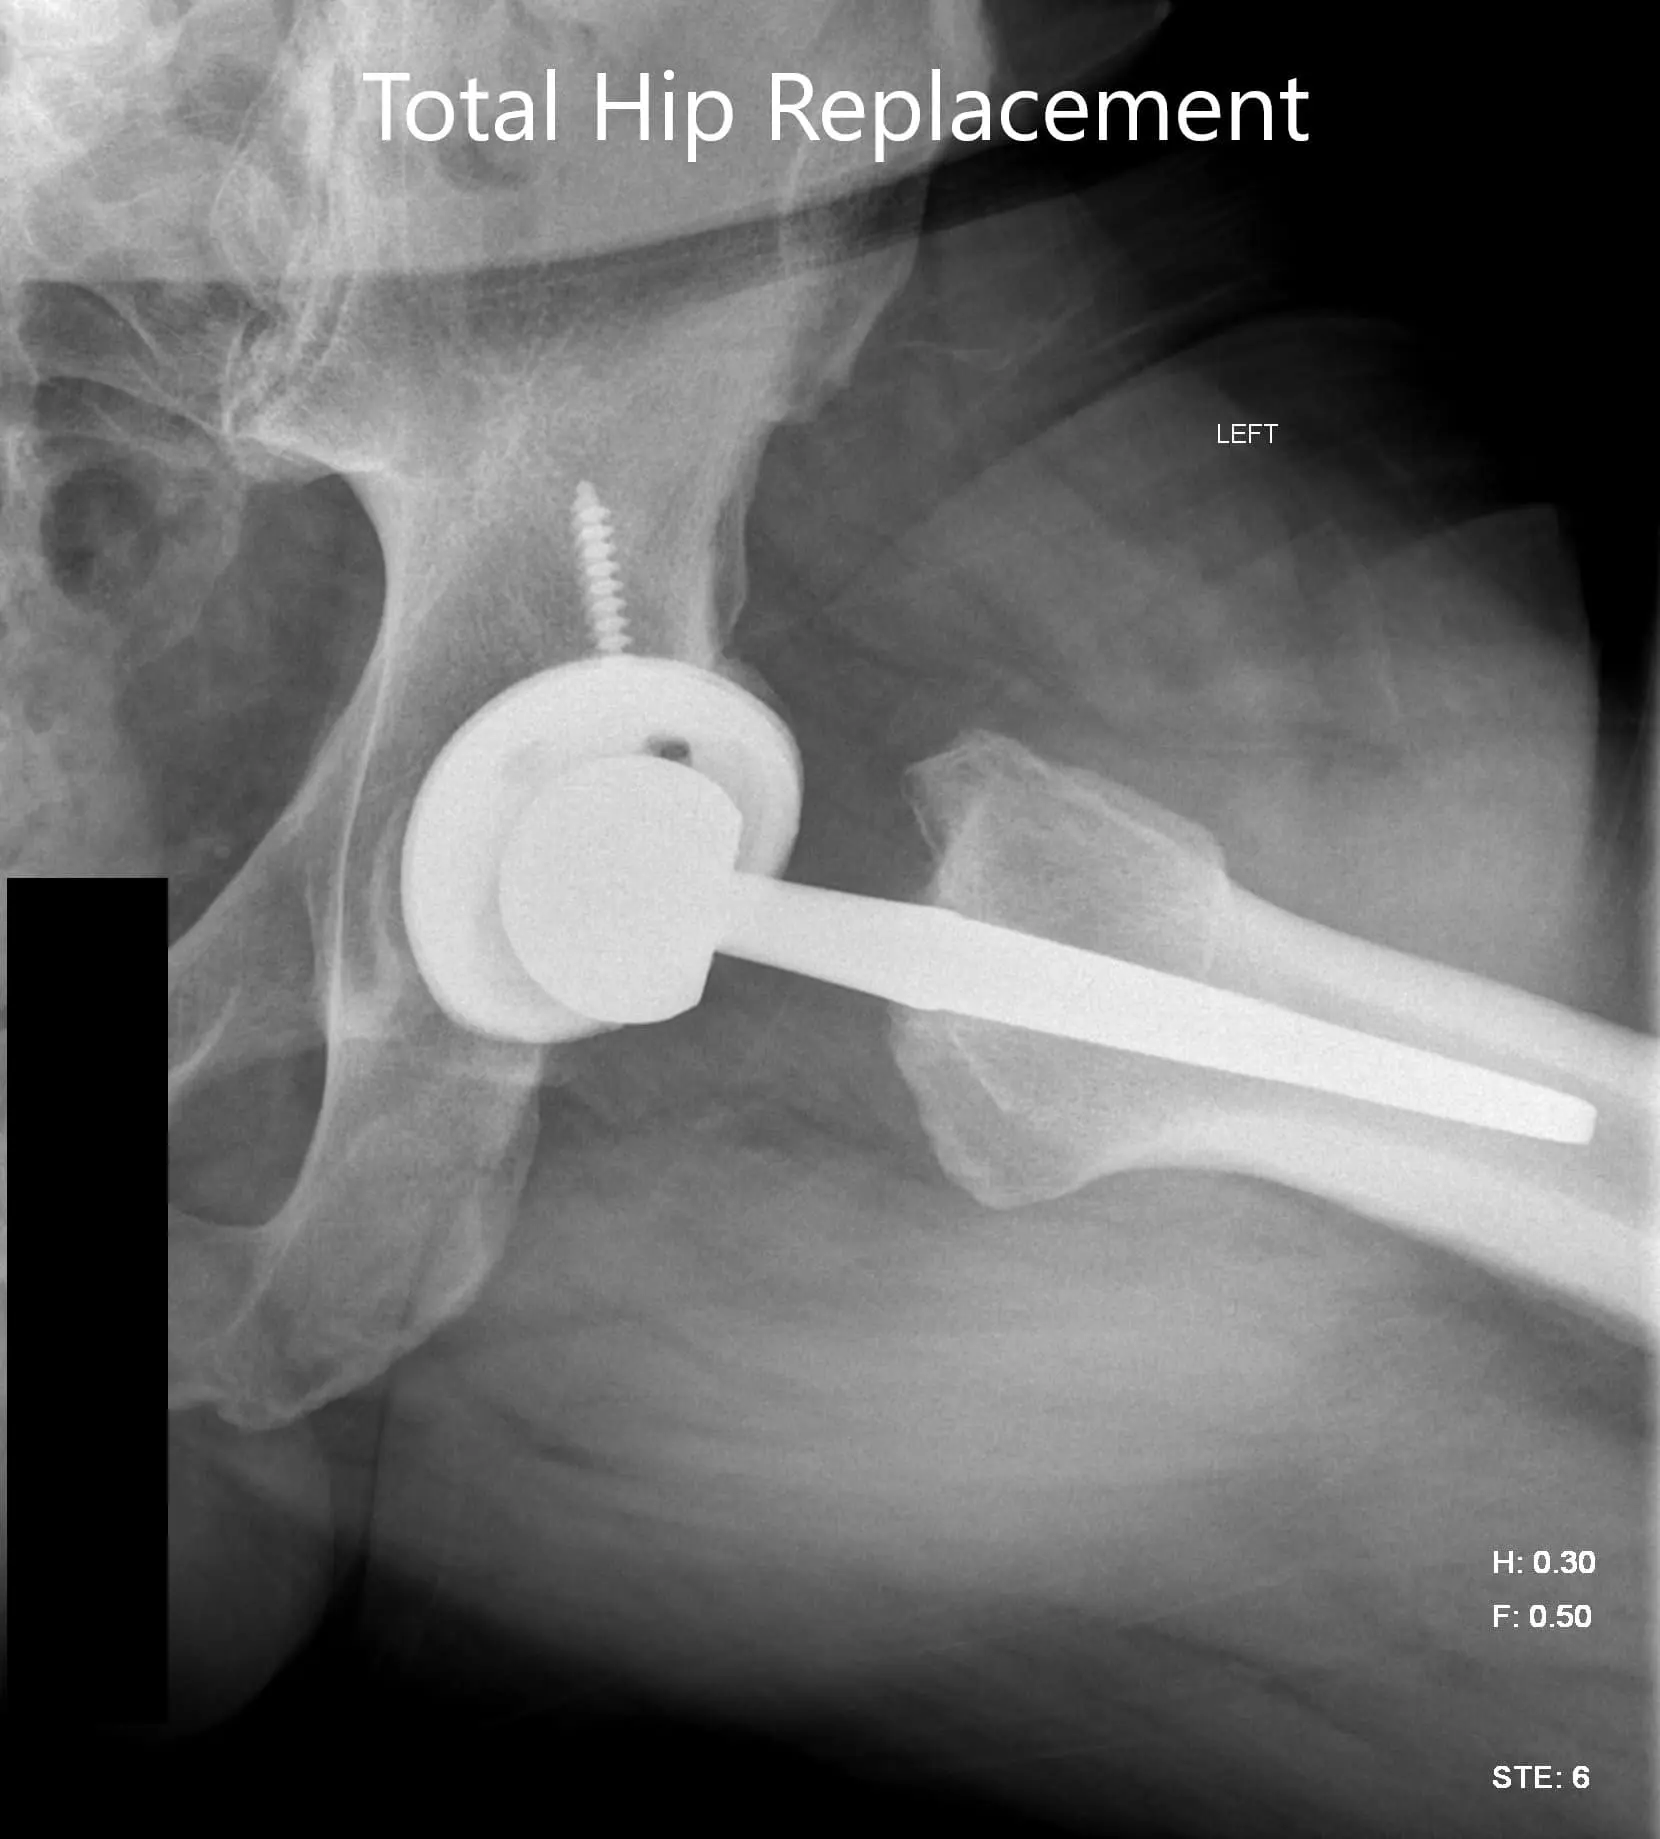

Implant used: Titanium hemispherical shell 60 mm with a 6.5 cancellous screw, 6.5 mm in diameter, 35 mm in length with ceramic femoral head 36 mm, 0-degree polyethylene with 127-degree neck angle hip stem size 5.

Postoperative X-ray images showing AP view and frog legged lateral view.